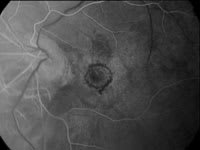

Novartis Ophthalmics has announced the results of two clinical trials on the effectiveness of Visudyne therapy. Both studies were multicenter phase IIIb randomized, placebo-controlled studies.

The first study showed that Visudyne therapy benefits wet age-related macular degeneration (AMD) patients with occult choroidal neovascularization (CNV). The second study showed that Visudyne reduces the risk of vision loss in patients with CNV due to pathologic myopia.

Clinical results show that Visudyne benefits two types of patients. |

In the first study, 339 AMD patients enrolled at 28 centers throughout North America and Europe. After 24 months, 46% of the enrollment population treated with Visudyne lost less than three lines of vision on a standard eye chart, compared to 33% of the placebo group. The difference of 13% between the treated group and the placebo group is statistically significant and higher than the 4% difference seen after 12 months of Visudyne treatment.

In the second study, investigators treated 120 patients with CNV due to pathologic myopia. After 12 months, 86% of the patients treated with Visudyne lost less than three lines of vision on a standard eye chart, compared to 67% of the placebo group (a difference of 19%). After 24 months, the difference dropped from 19% to 7%, still in favor of Visudyne. However, 40% of the Visudyne-treated patients gained one or more lines of vision versus 13% of the placebo group.

In both studies, patients treated with Visudyne received, on average, five treatments over 24 months. Investigators found no new safety concerns.